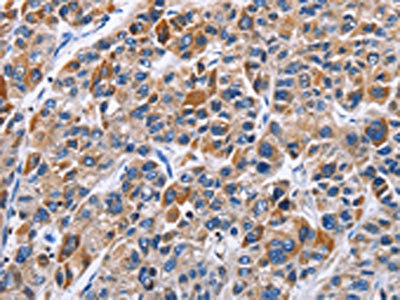

The image on the left is immunohistochemistry of paraffin-embedded Human liver cancer tissue using CSB-PA598713(ENPP5 Antibody) at dilution 1/40, on the right is treated with fusion protein. (Original magnification: ×200)